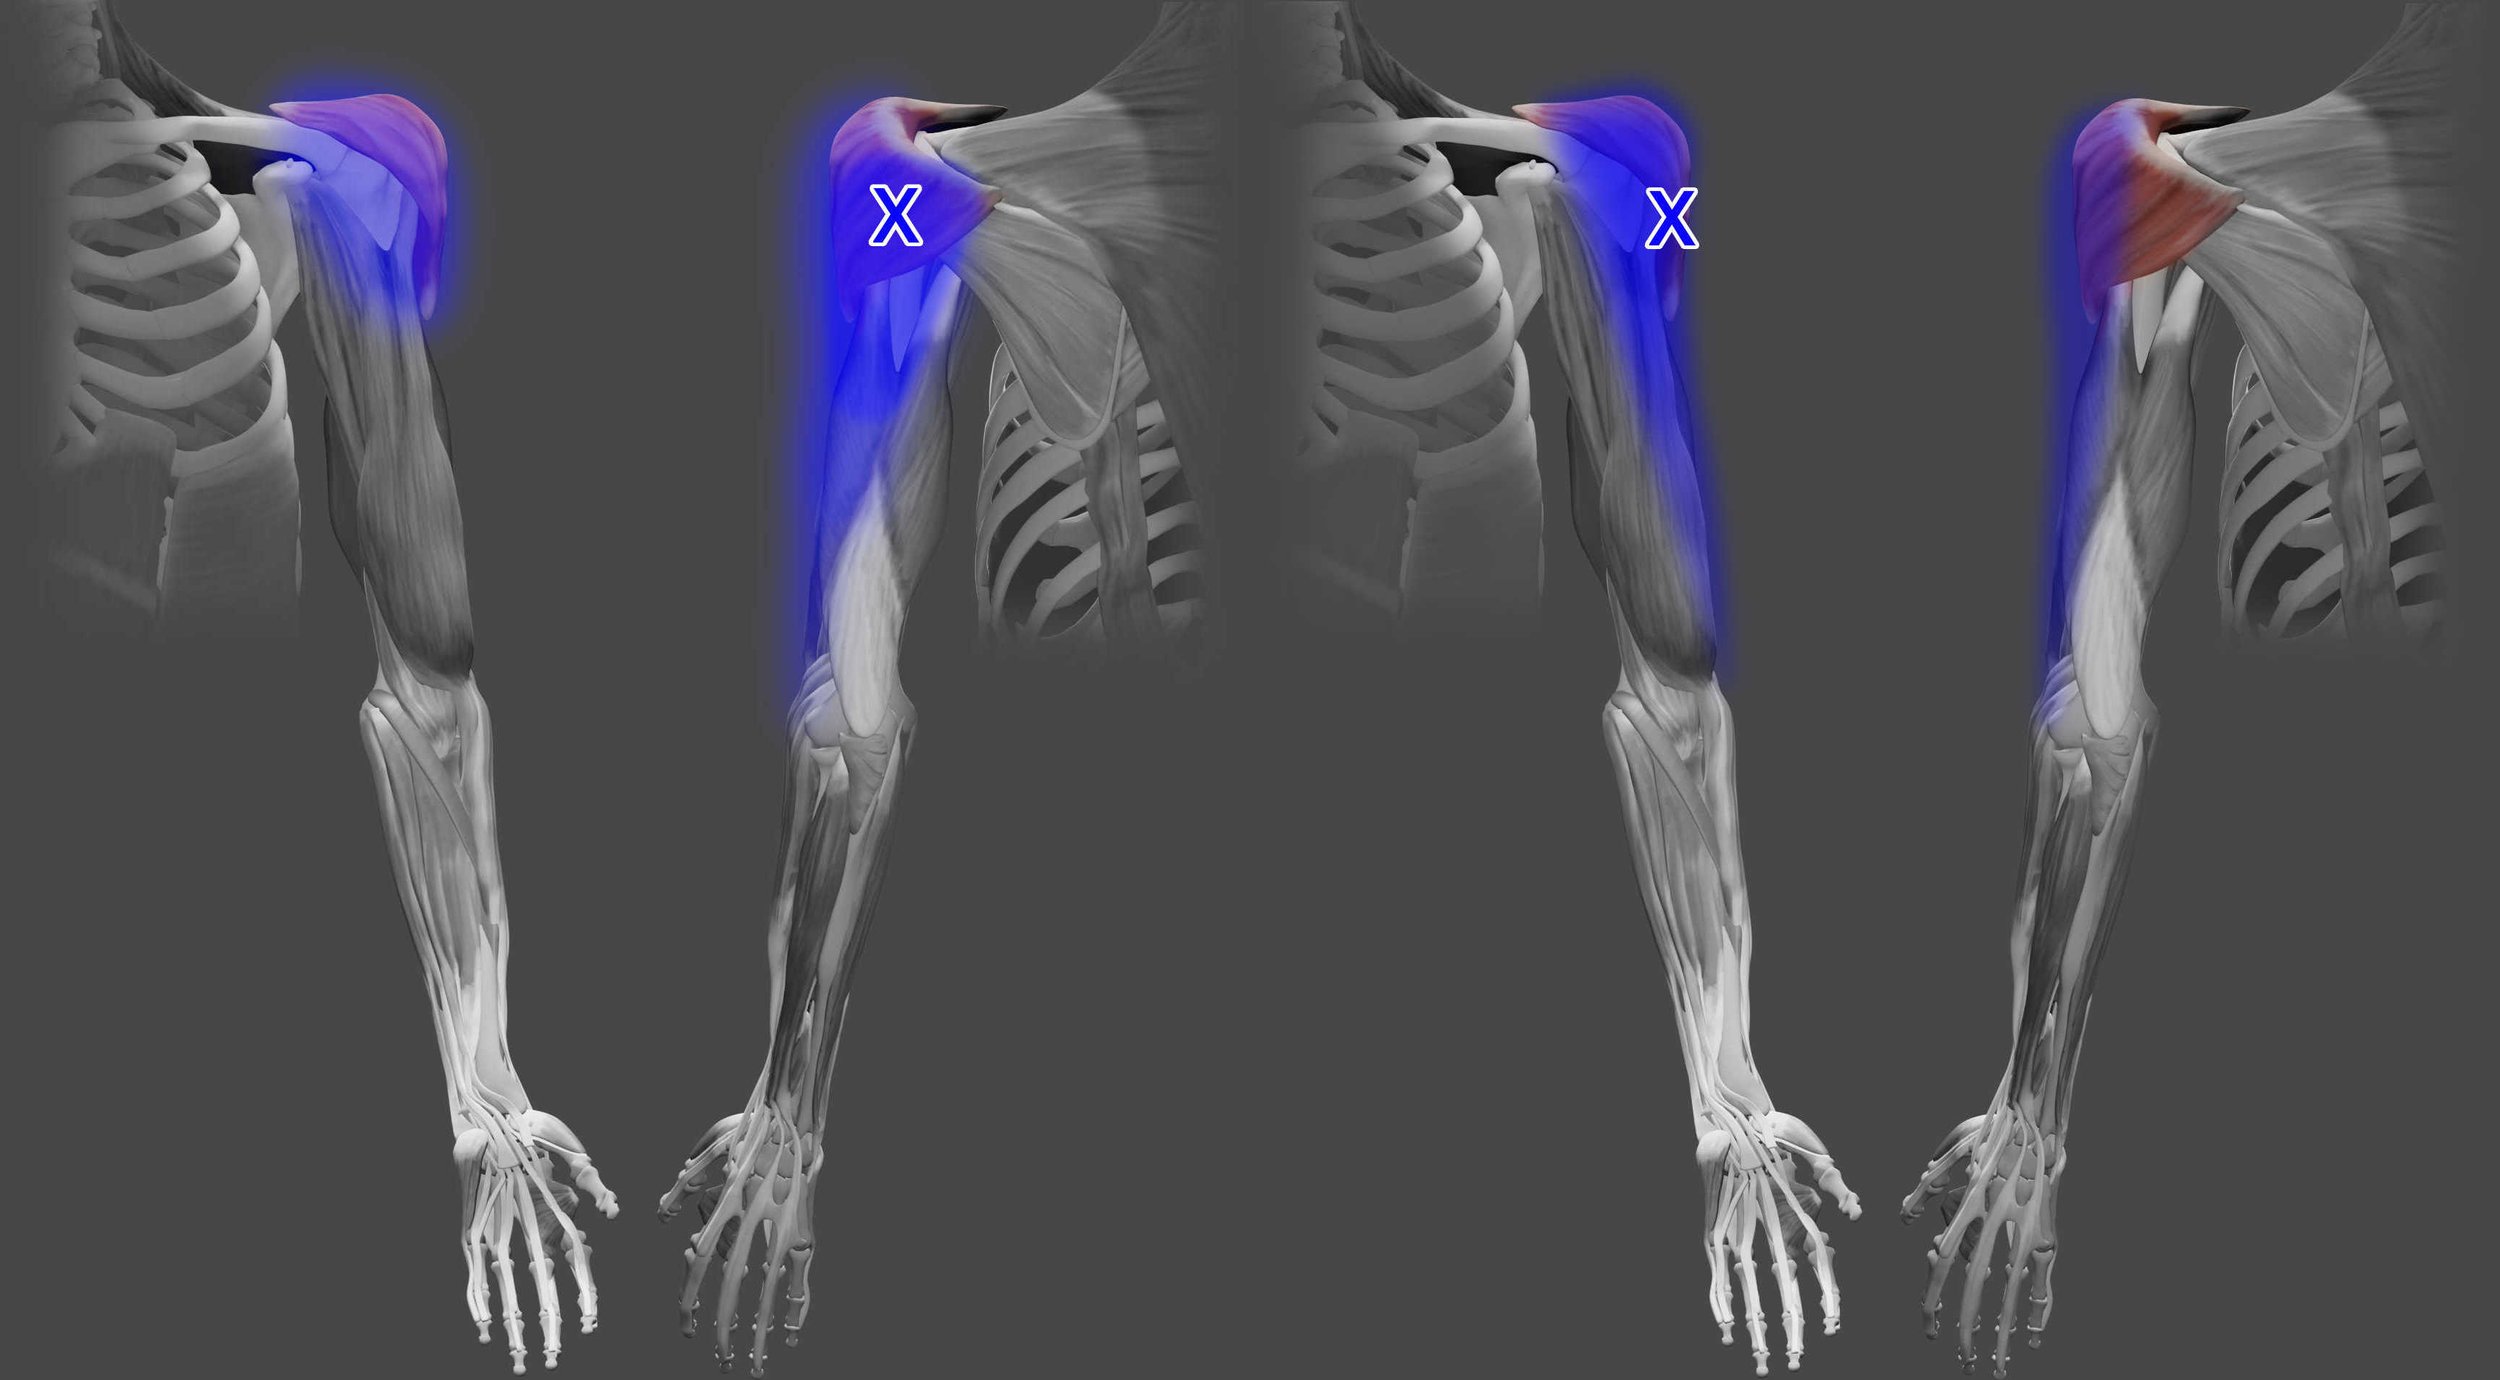

Acupuncture for Teres Major Pain

Teres major trigger points can cause back of arm, back of shoulder, and dorsal forearm pain. Learn more about teres major pain and how acupuncture and dry needling can help.

Acupuncture for Deltoid Pain

Deltoid trigger points commonly cause localized shoulder pain. Learn more about the deltoid muscle, causes of pain, and how acupuncture and dry needling can help with deltoid pain.

Acupuncture for Teres Minor Pain

Teres minor trigger points can cause posterior shoulder pain as well as numbness and tingling of the 4th and 5th fingers that can mimic cervical radiculopathy. Learn more about the teres minor muscle, causes of pain, and how acupuncture and dry needling can help.